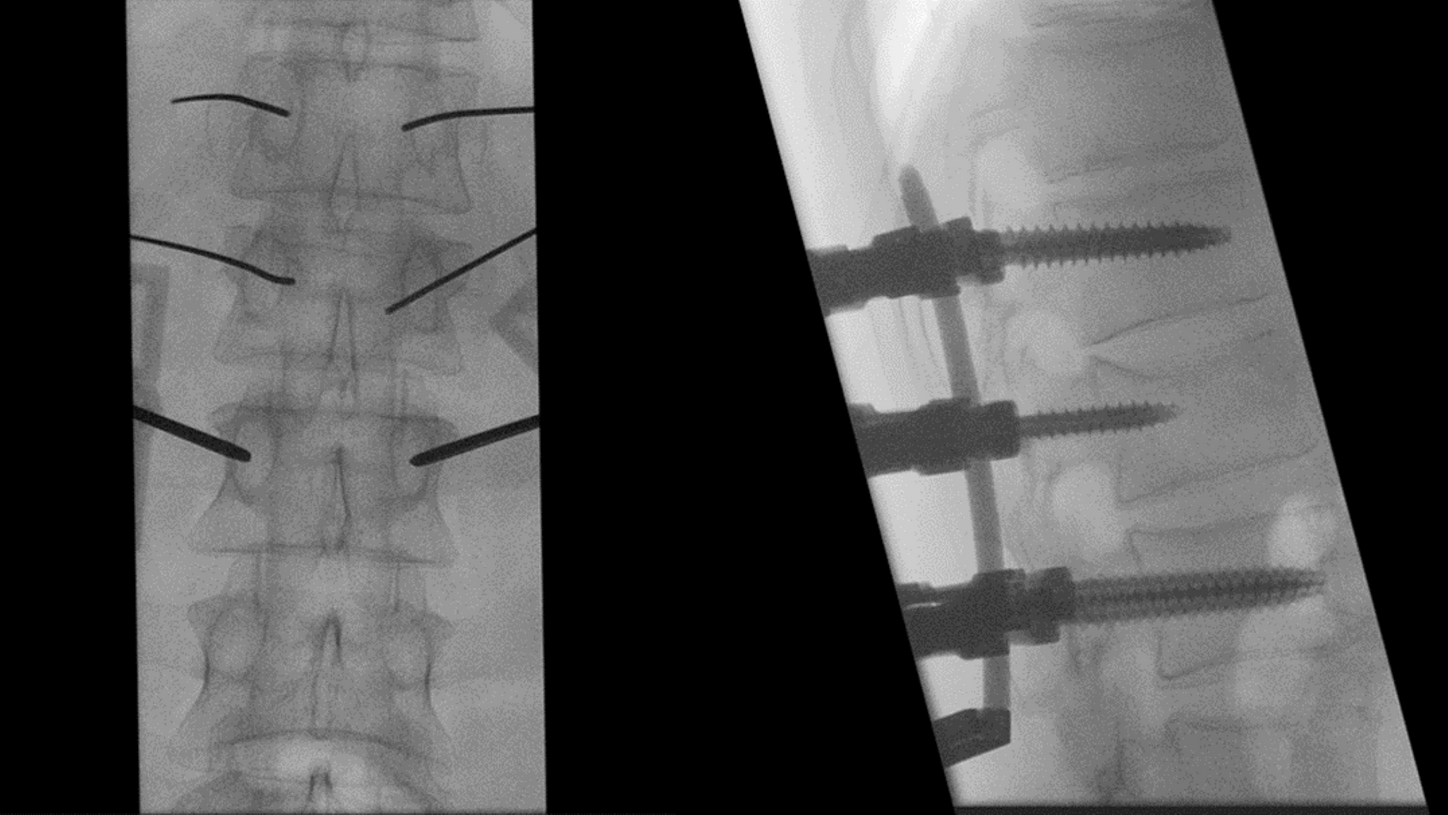

A preclinical study confirmed intraoperative-imaging time savings of up to 55% in pelvic surgery, enabled by the self-driving and automation technologies of CIARTIC Move.

CIARTIC Move already has proven its benefits in a preclinical study1: The system enabled significant time savings for all three anatomical regions included in the study (pelvis, spine, distal radius).